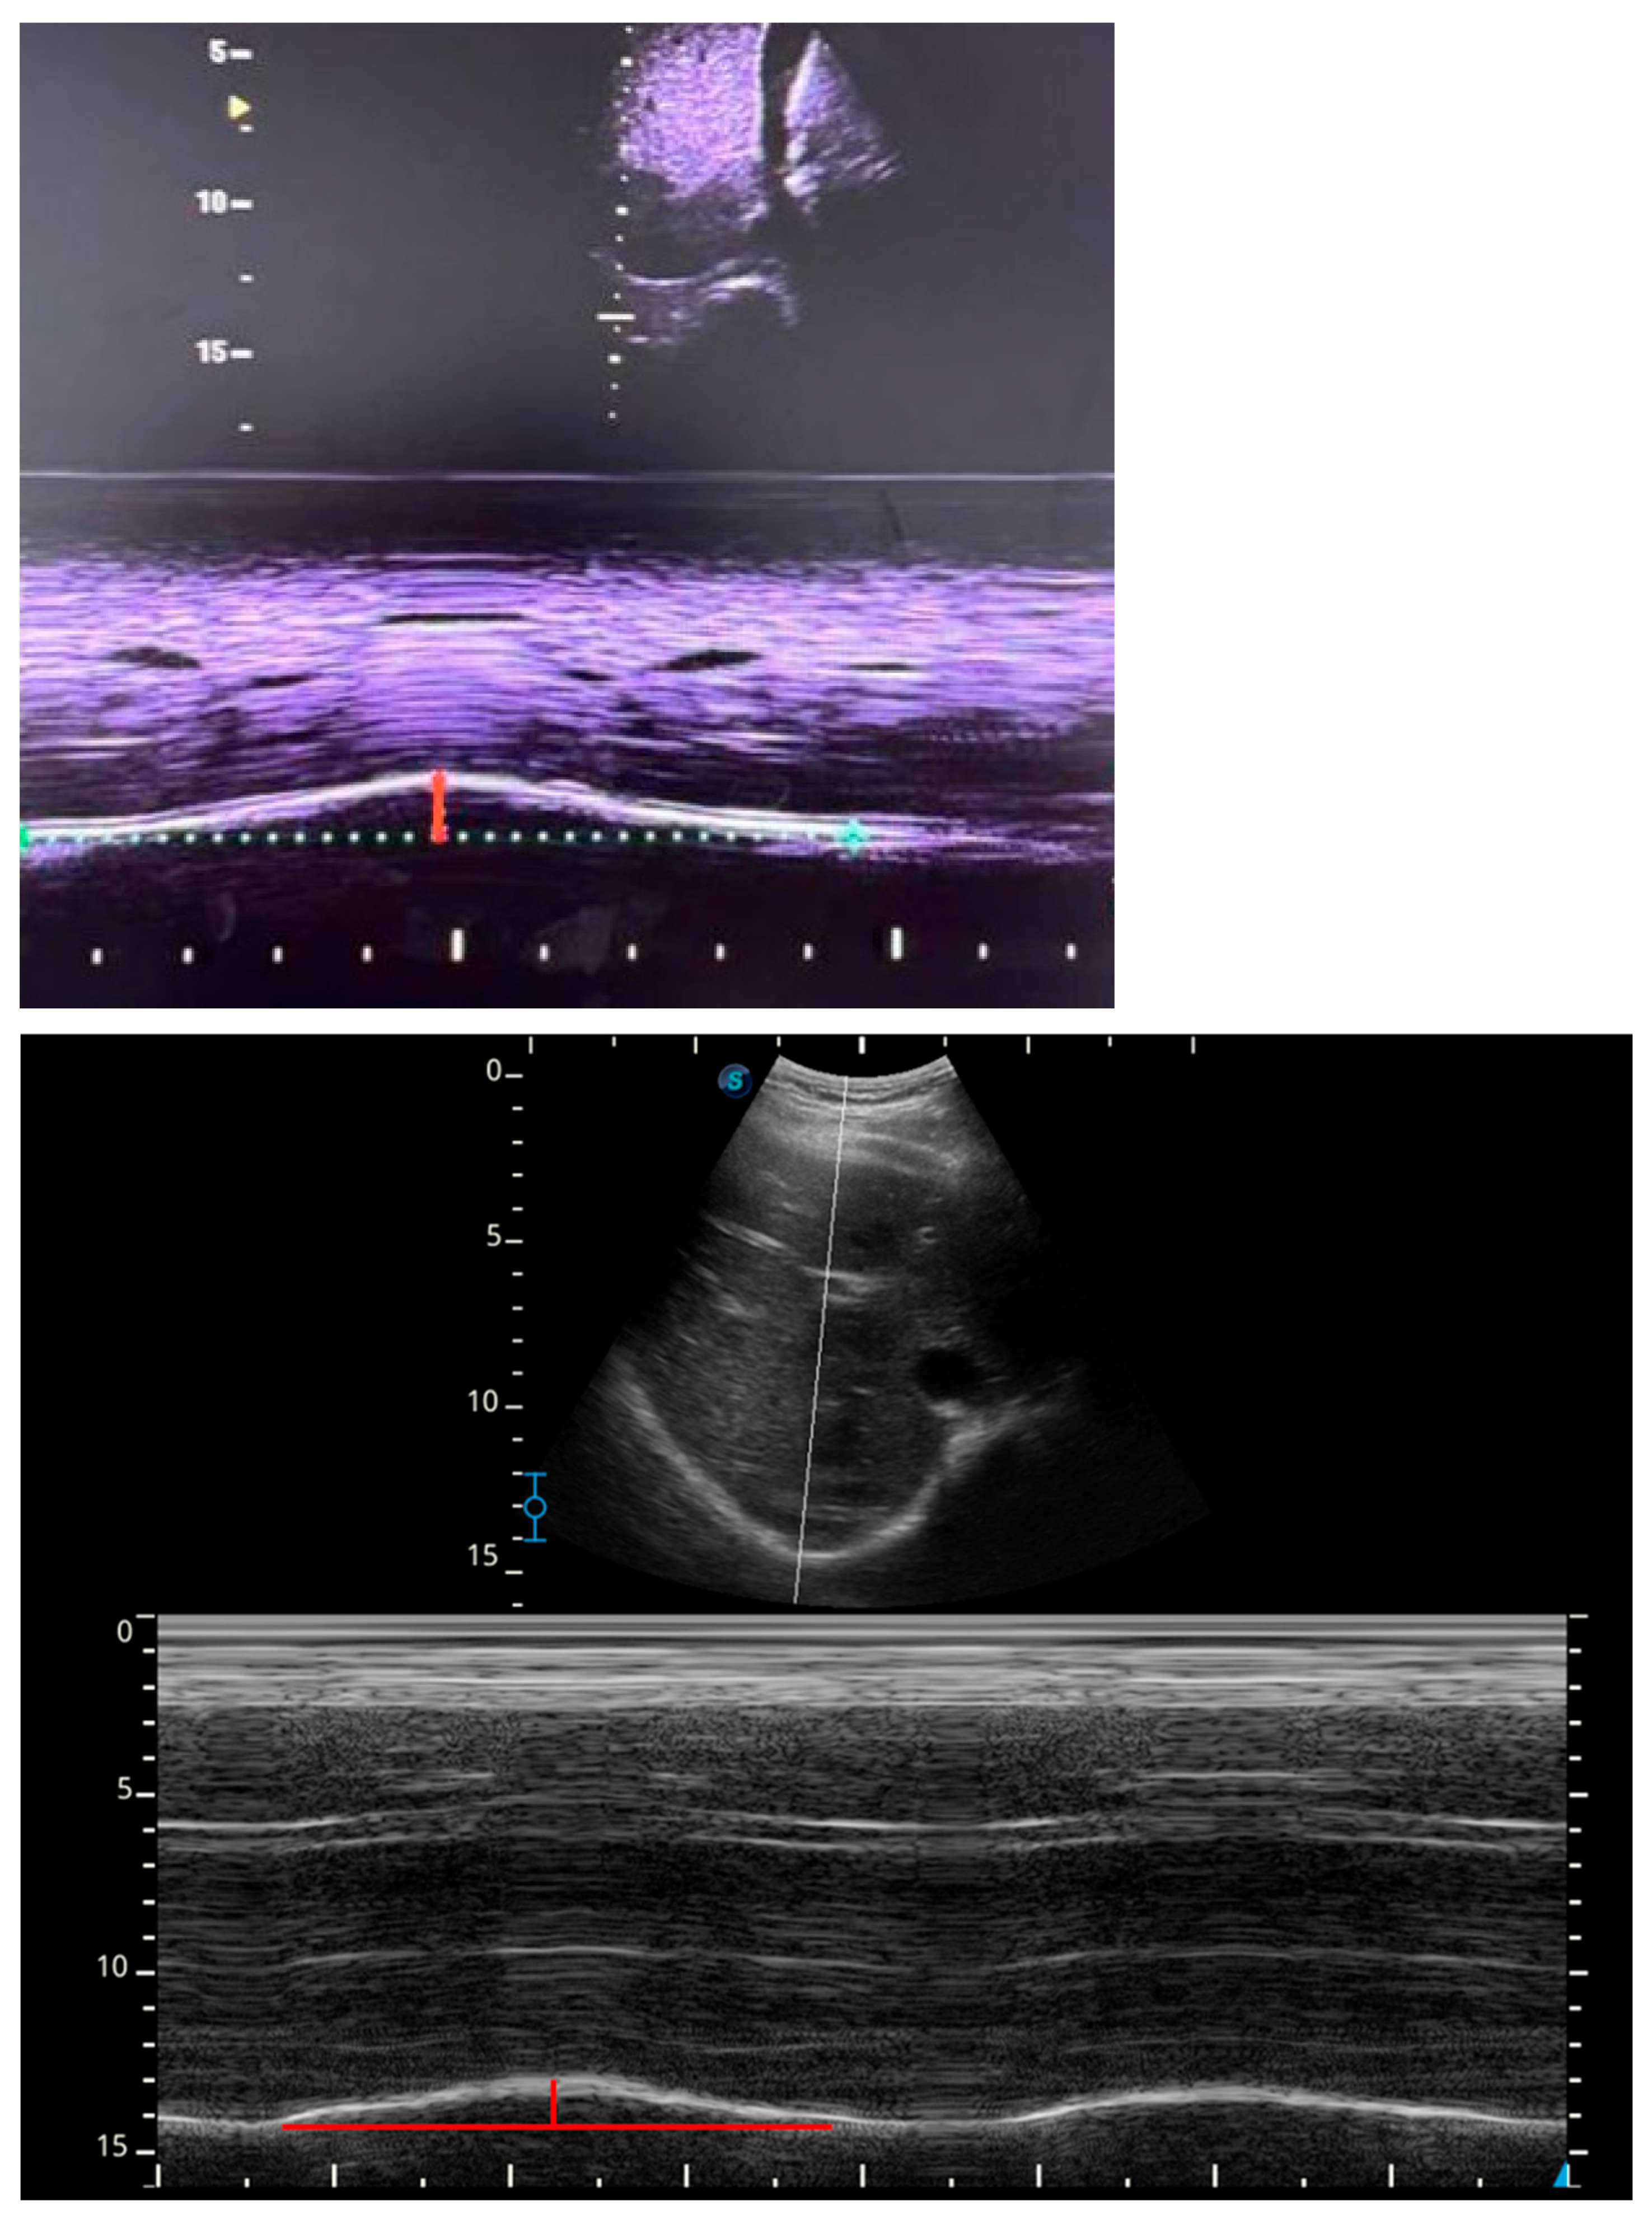

The ultrasound mode was then switched to M-mode to visualize diaphragmatic movement. The M-mode sweep speed was maintained using the standardized default setting of the ultrasound system, in accordance with international expert consensus recommendations. Once a clear image was obtained, the image was frozen, and diaphragmatic excursion was measured in centimeters from the baseline to the point of maximal displacement. In each body position, three consecutive measurements were obtained and subsequently averaged for statistical analysis. A two-minute stabilization period was observed after each positional change to allow physiological accommodation and stabilization of ventilation and intra-abdominal pressure, after which respiratory frequency stability was reconfirmed before initiating the subsequent measurement (Figure 1).

Figure 1.

Representative ultrasound image showing diaphragmatic excursion assessed using M-mode. The grayscale B-mode image (upper panel) illustrates probe positioning and diaphragm visualization, while the M-mode tracing (lower panel) depicts diaphragmatic motion over time. The colored horizontal line represents the baseline position of the diaphragm at end-expiration, and the colored vertical line indicates the maximal diaphragmatic displacement during inspiration. Diaphragmatic excursion was calculated as the distance between baseline and maximal inspiratory displacement.